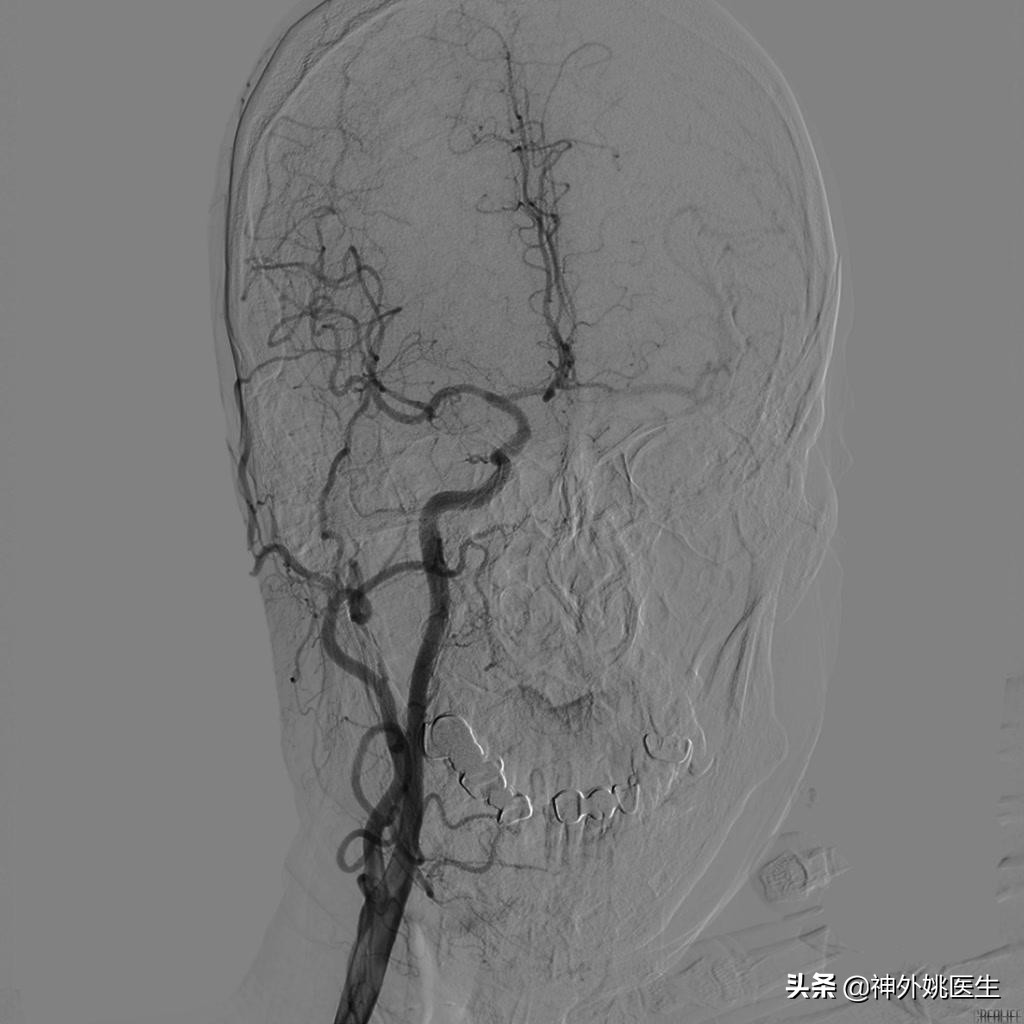

术前DSA检查:(图3-6)

图3 左颈内动脉起始段重度狭窄。

图4 右颈动脉造影示前交通动脉开放,左侧A2以远显影,通过左侧A1至M1以远亦显影。

图5 左侧颈动脉造影示左侧大脑前动脉显影欠佳。

图6 椎基底动脉造影示左侧后交通动脉开放,左侧大脑中动脉显影。